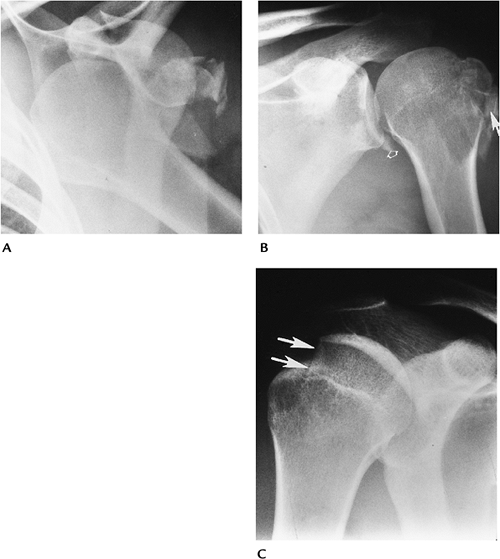

FIGURE 7-4 Anterior dislocations. (A) AP radiograph shows an anterior dislocation with fracture fragments laterally. (B) AP postreduction radiograph shows the tuberosity fracture (arrow) and Bankart lesion (open arrow) adjacent to the inferior glenoid. (C) AP radiograph demonstrates an impaction fracture (arrows) or Hill-Sachs lesion in a patient with a prior dislocation.

FIGURE 7-5 Posterior dislocations. (A) AP radiograph showing overlap of the glenoid and humeral head with an anteromedial impaction fracture (arrowheads). The humerus is fixed in internal rotation. (B) Scapular “Y” view clearly showing the posterior dislocation of the humeral head. Axial (C) and sagittal (D) CT images demonstrate the position of the head and the humeral head fracture (arrow).